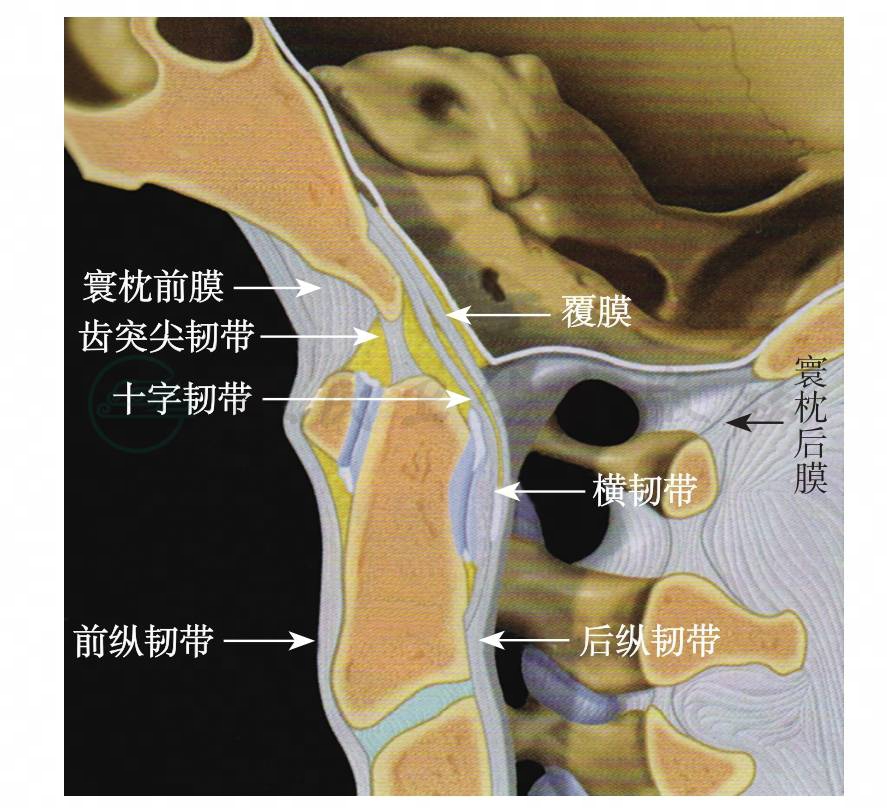

寰枕关节由枕骨髁与寰椎上关节面组成(图1),关节囊以及枕骨大孔与寰椎之间的寰枕前、后膜共同维持关节的稳定性。而枕骨与枢椎之间的覆膜、翼状韧带和齿突尖韧带等也参与维持其稳定性(图2,图3)。关节的过伸运动主要受覆膜的限制,过屈运动则受到颅骨与寰椎前缘的骨性接触限制。侧弯和旋转运动主要受翼状韧带的限制。寰枕关节的活动范围为:屈25°→←伸25°,左右侧屈以及一侧轴向旋转范围均为5°。由于寰枕关节紧邻脑干、脑神经及椎动脉,如骨折同时造成这些结构的损伤,可导致部分病例在得到救治之前死亡。但有些经过抢救幸存的患者中,经过治疗后甚至能够完全康复。该病在儿童的发生率大于成人,由于儿童的枕骨髁发育未完善,寰枕关节面较平坦且易脱位,其关节周围的韧带较为松弛,因此其关节的稳定性较差。

图3 枕颈部关节韧带